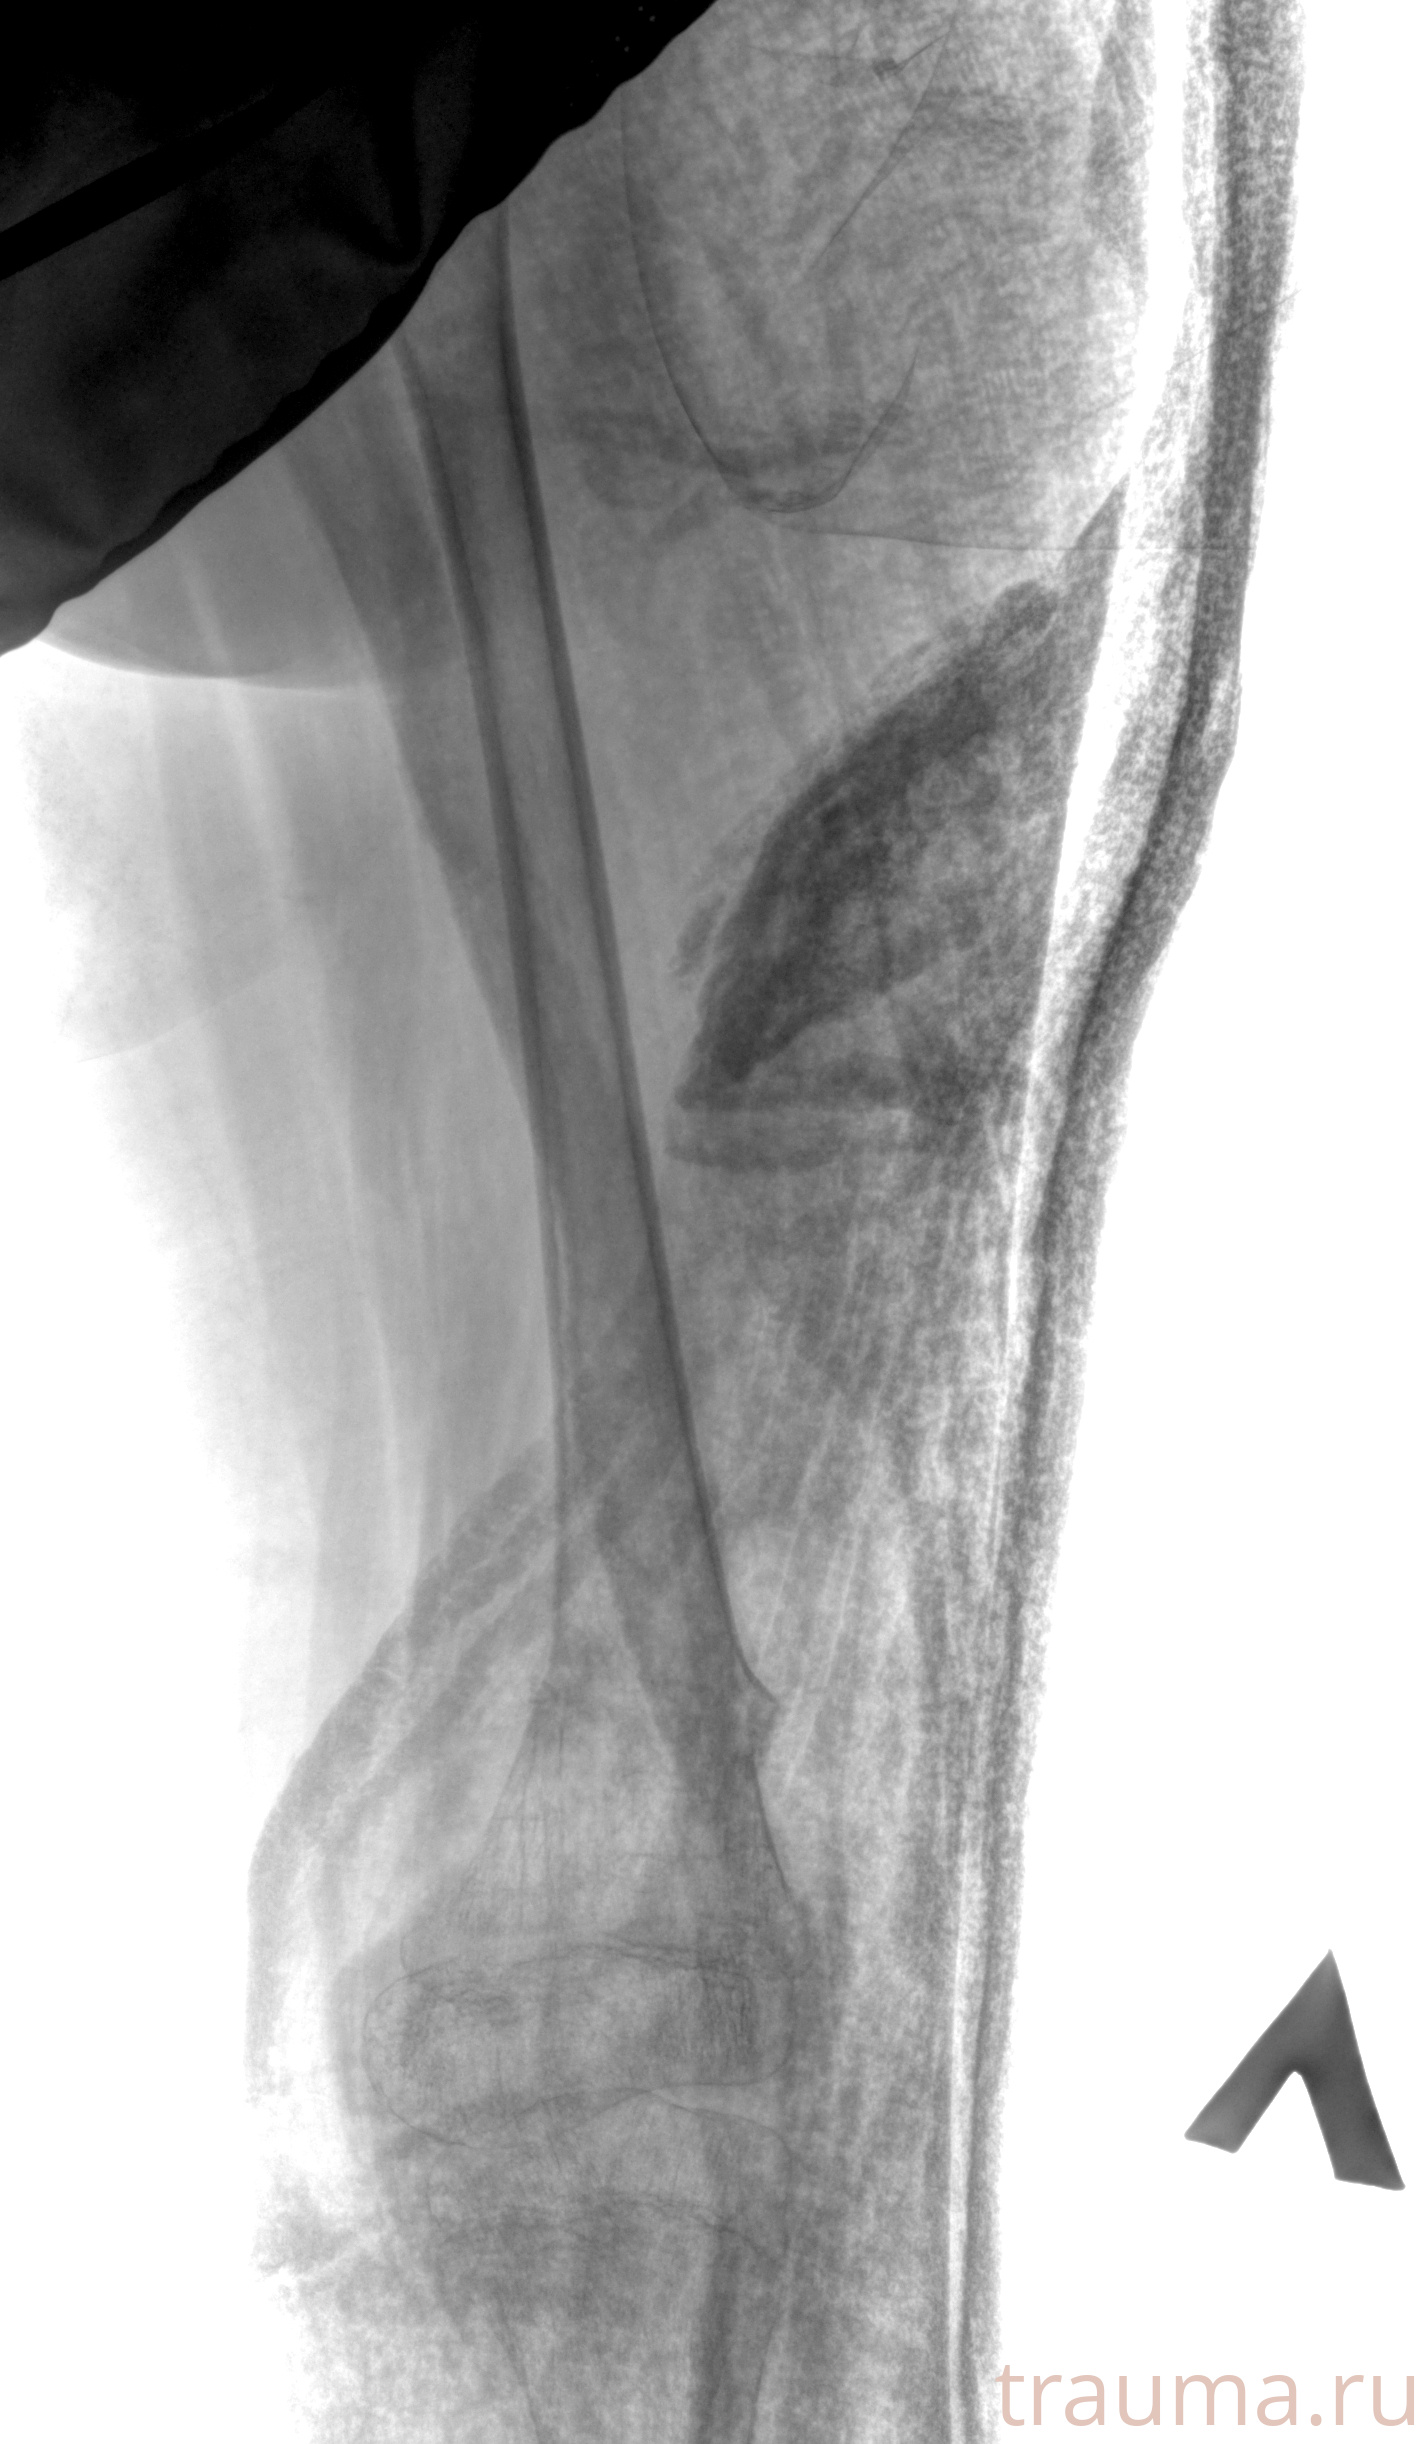

Рентген на дому: по вашему адресу приезжает врач-рентгенолог, травматолог-ортопед с мобильным рентгеновским аппаратом, проводит диагностику травмы или заболевания, делает необходимые рентгенограммы, дает рекомендации по дальнейшему лечению. Получить качественные снимки в домашних условиях возможно благодаря уникальной методике, разработанной МосРентген Центром для института  Склифосовского